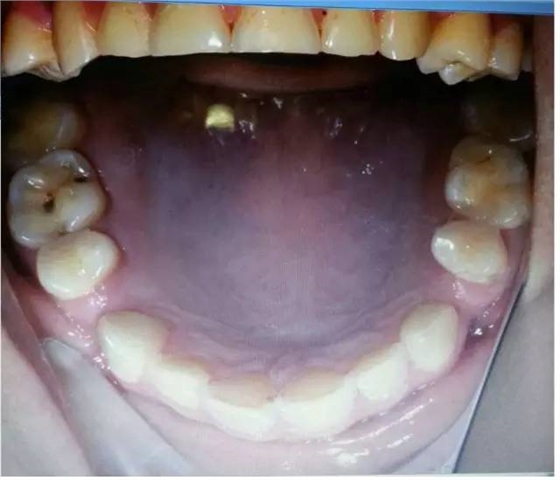

磨耗是超過(guò)生理范圍的牙體磨損,是一種病理性磨損,臨床上磨損可并發(fā)各種病癥或?yàn)橹虏∫蛩兀缫鹧辣举|(zhì)過(guò)敏、食物嵌塞、牙髓炎、顳頜關(guān)節(jié)病,以及口內(nèi)軟組織創(chuàng)傷性潰瘍,并可成為致癌的因素。

過(guò)大的(牙合)力通常是造成磨耗的原因,還有醫(yī)生指出,如患嬰兒式吞咽方式,舌頭在吞咽時(shí)會(huì)對(duì)牙齒產(chǎn)生推力,導(dǎo)致應(yīng)力集中的頸部出現(xiàn)微折裂也是原因之一。以上幾點(diǎn)都是造成牙體缺損的機(jī)械因素哦!其實(shí)這個(gè)病例給了我們很多信息,需要我們細(xì)致的檢查和問(wèn)診,來(lái)吧,跟著權(quán)老師探究隱藏在表象之下的真相:牙齒出現(xiàn)缺損除了機(jī)械因素,還有什么因素?

是的,牙齒缺損還可能是化學(xué)因素造成的。權(quán)老師追問(wèn)患者是否有胃病,追問(wèn)飲食習(xí)慣,果真發(fā)現(xiàn)諸多玄妙之處。“患者喜歡吃酸東西,每頓飯必吃醋,吃完馬上就刷牙。”沒(méi)想到吧,這些看似不起眼的飲食習(xí)慣也能探究出與牙齒磨耗的因果關(guān)系,難怪群里郭耀銘老師忍不住感嘆權(quán)老師分享的病例酸味十足哩!這種酸酸的味道是要讓大家學(xué)會(huì)分辨機(jī)械因素和化學(xué)因素導(dǎo)致的牙體缺損。